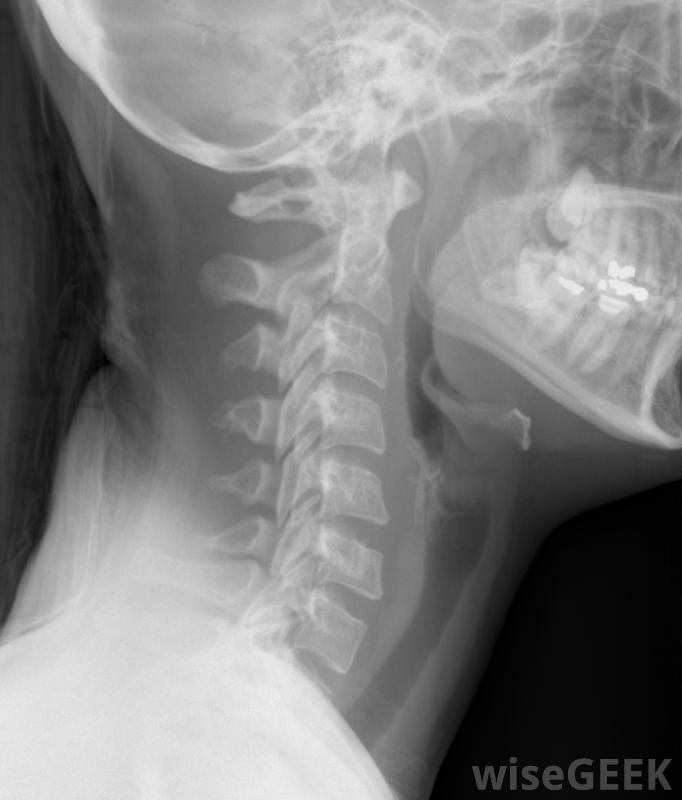

对包括颈椎在内的颈部进行的X光检查。当身体出现机械性紊乱时,这种紊乱会干扰神经向大脑发送的信息。这会导致神经功能不正常。身体的大部分部分依靠中枢神经系统来工作顺利,所以当脊柱出现半脱位时,这种理论认为,一个人的整体健康状况会恶化。